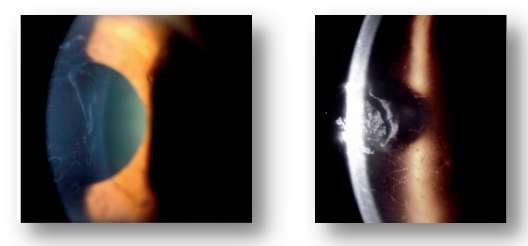

Figure 1. Primary corneal epithelial lesions. The left picture shows corneal epithelial basement membrane dystrophy, and the right picture shows corneal lattice dystrophy

1. Corneal epithelial basement membrane dystrophy (also known as map dot fingerprint dystrophy), which is due to the abnormal development of corneal epithelial basement membrane, resulting in repeated epithelial loss;

2. Corneal lattice dystrophy is characterized by irregular branching white thin strips and turbid spots in the superficial parenchyma and Bowman's layers, which gradually expand, thicken and increase, and interweave into a grid; It may also be accompanied by recurrent epithelial defects.